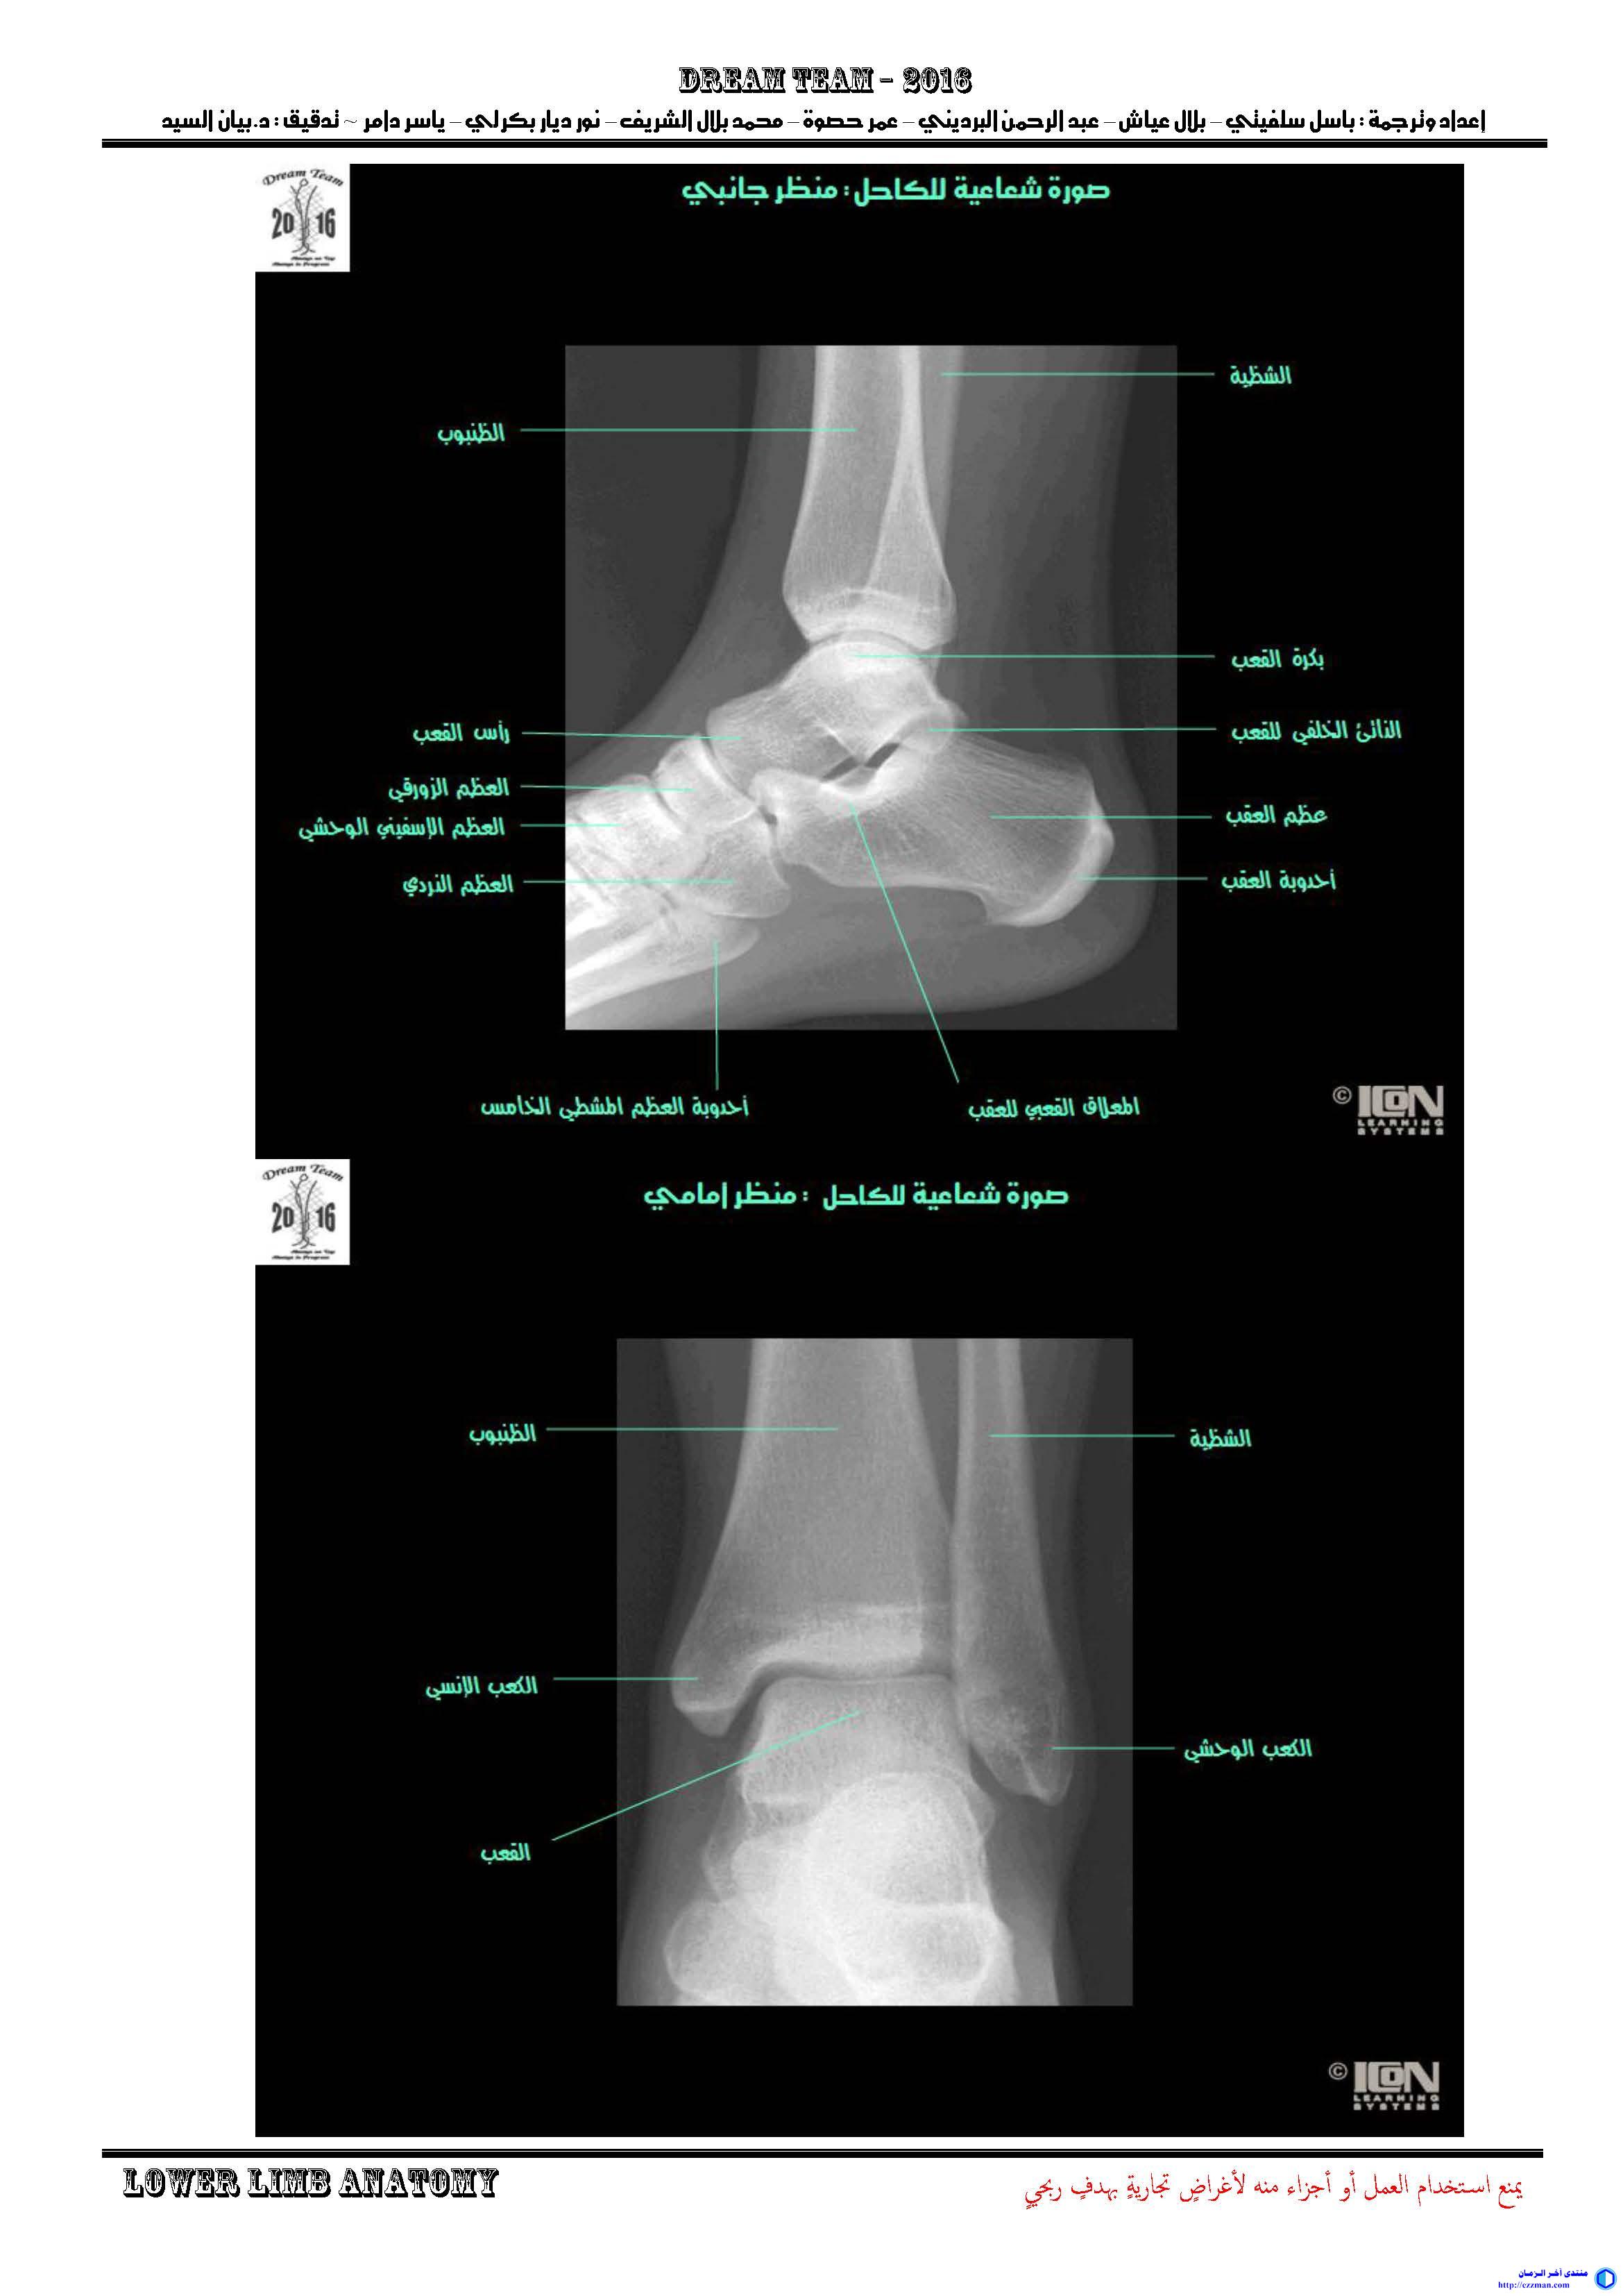

-   -   أطلس التشريح Netter [الجزء 8 الطرف السفلي] (https://www.ezzman.com/vb/t3726/)